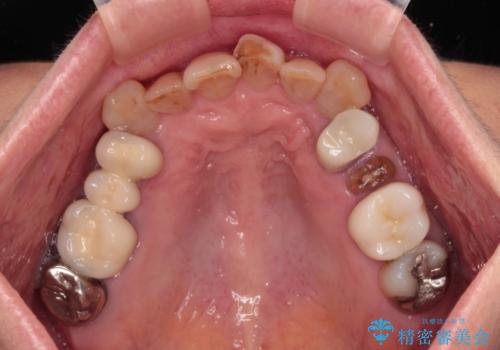

- 長年気にしていた捻れた前歯が欠けたとのことで来院された患者様です。

矯正治療に抵抗があったそうですが、前歯が欠けたことをきっかけに、矯正治療で歯列を整えた上で、セラミッククラウン治療を行う決心が付いたとのことでした。

デコボコが強いため、ブリッジや残根となっている部分のスペースを利用して歯列を整え、変色や欠けている歯をオールセラミッククラウンによる補綴治療を行うこととしました。

歯肉移植などによる前歯部の歯肉ライン改善を提案しましたが、口を開けたときにほとんど見えないので気にならないとのことで、特に処置を行うことなく補綴治療を行いました。